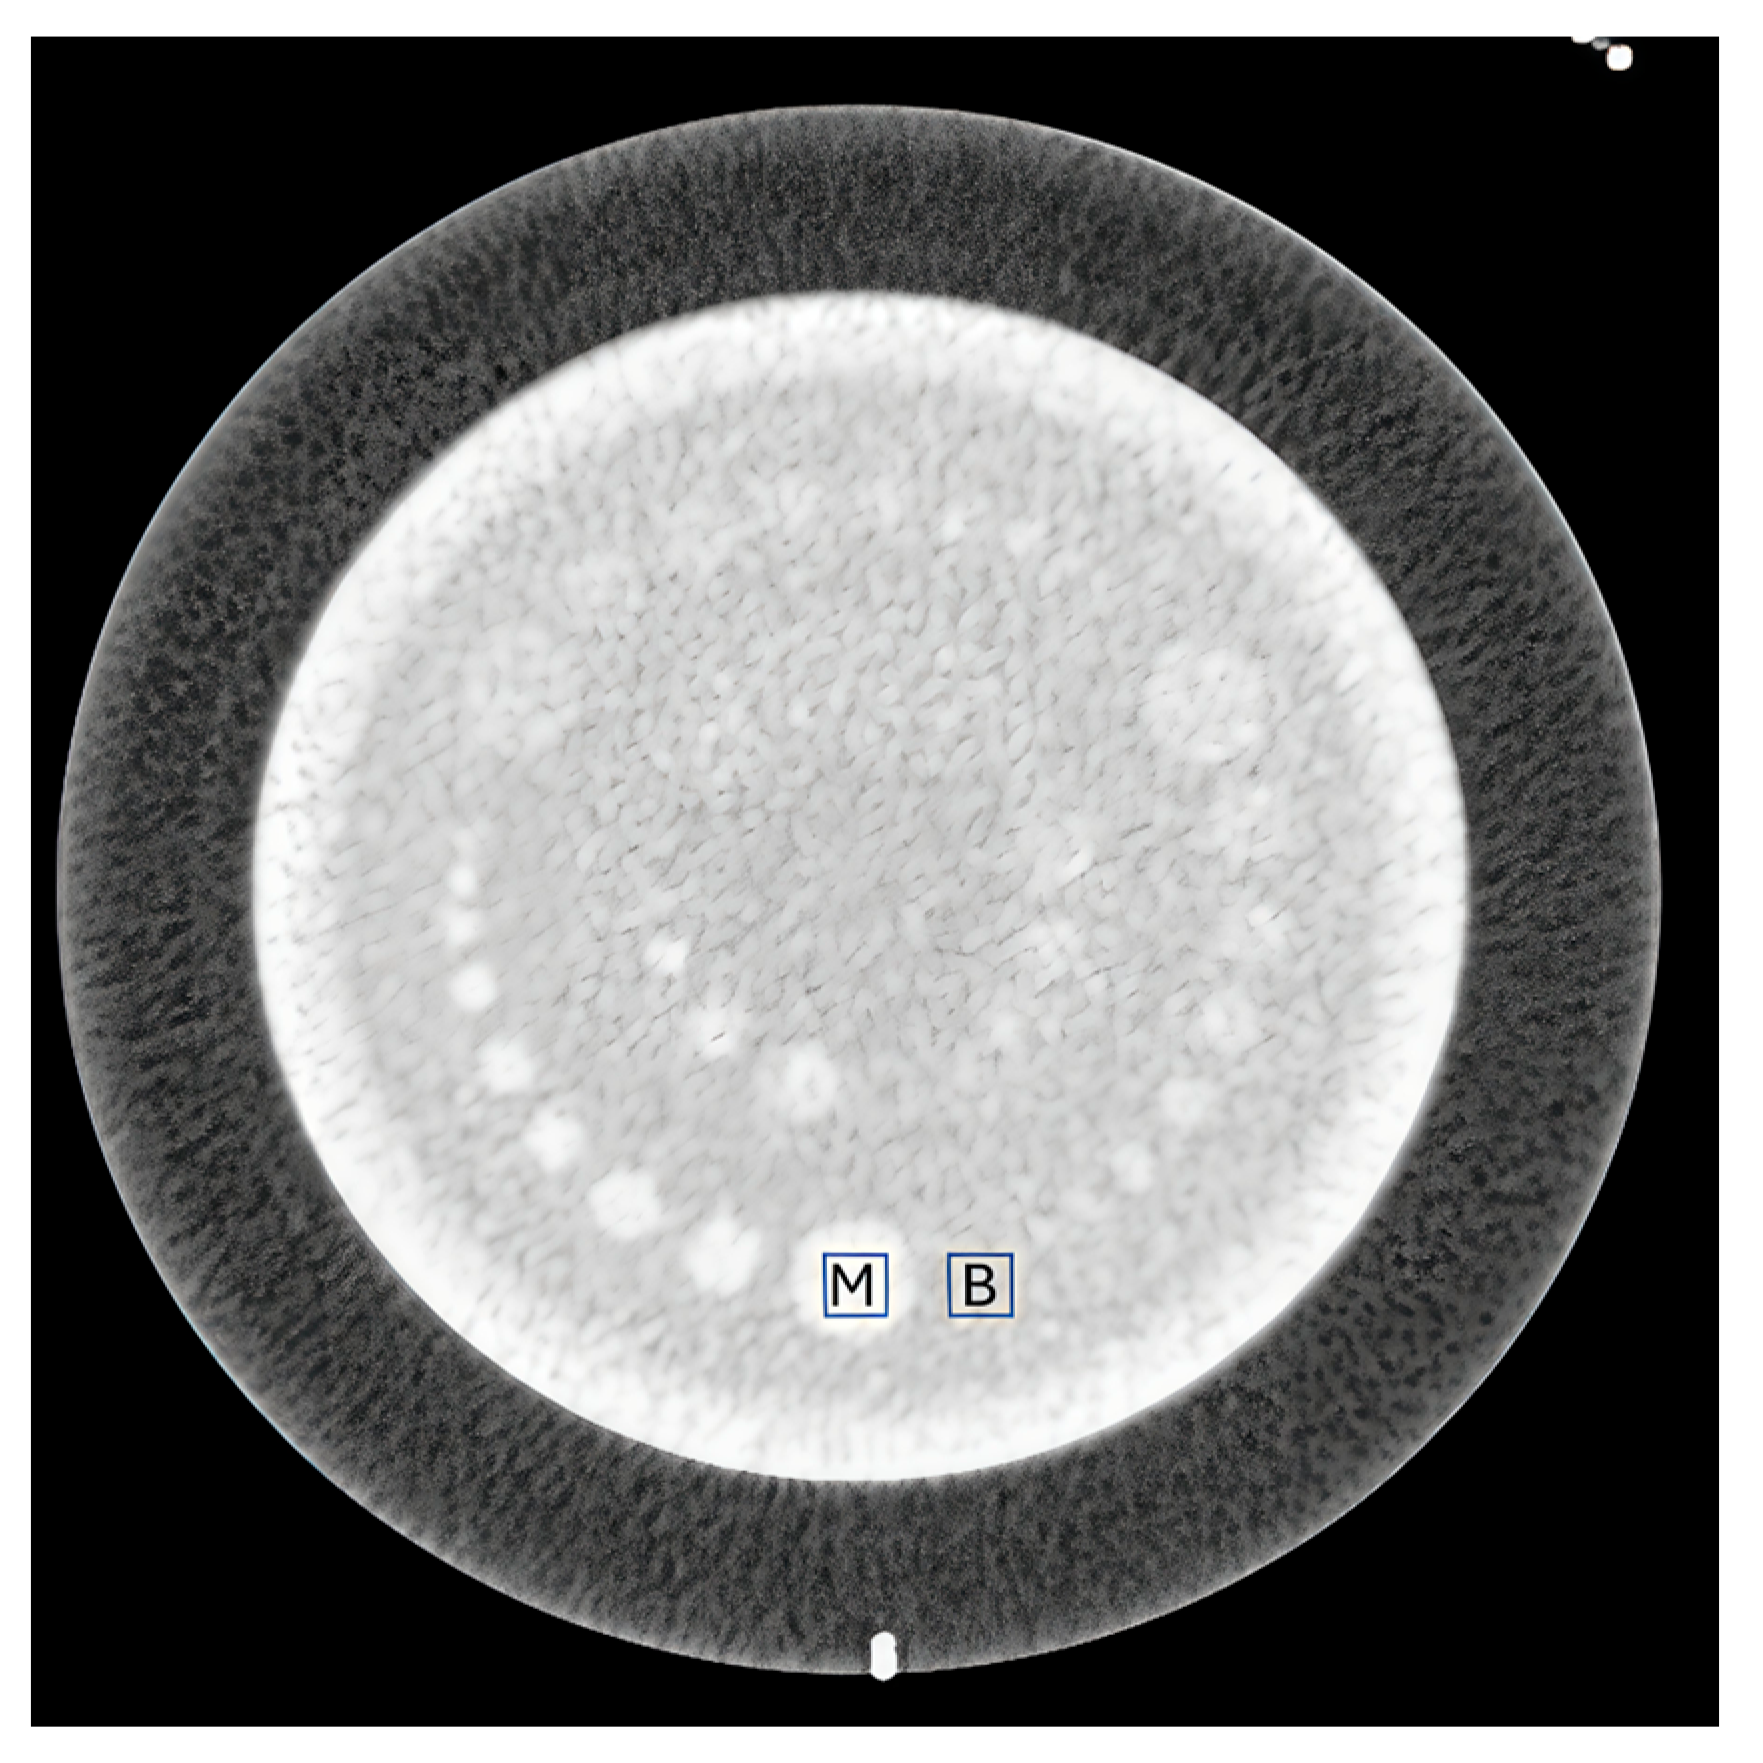

2.3. CT Systems and Phantom Experiments

2.4. Image Quality Assessment

3.1. CT Values

3.2. Noise (SD) Values

3.3. Relationship Between CNR and Dose